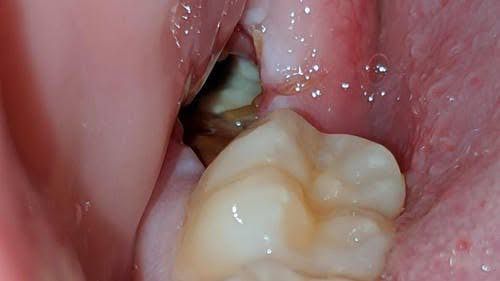

Dry socket (alveolar osteitis) is a painful dental condition that sometimes happens after you have a permanent adult tooth extracted. Dry socket is when the blood clot at the site of the tooth extraction fails to develop, or it dislodges or dissolves before the wound has healed.